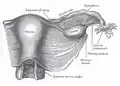

Útero e ligamento largo direito, vistos por trás

Útero e ligamento largo direito, vistos por trás -